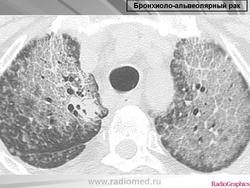

Бронхиолоальвеолярный рак.